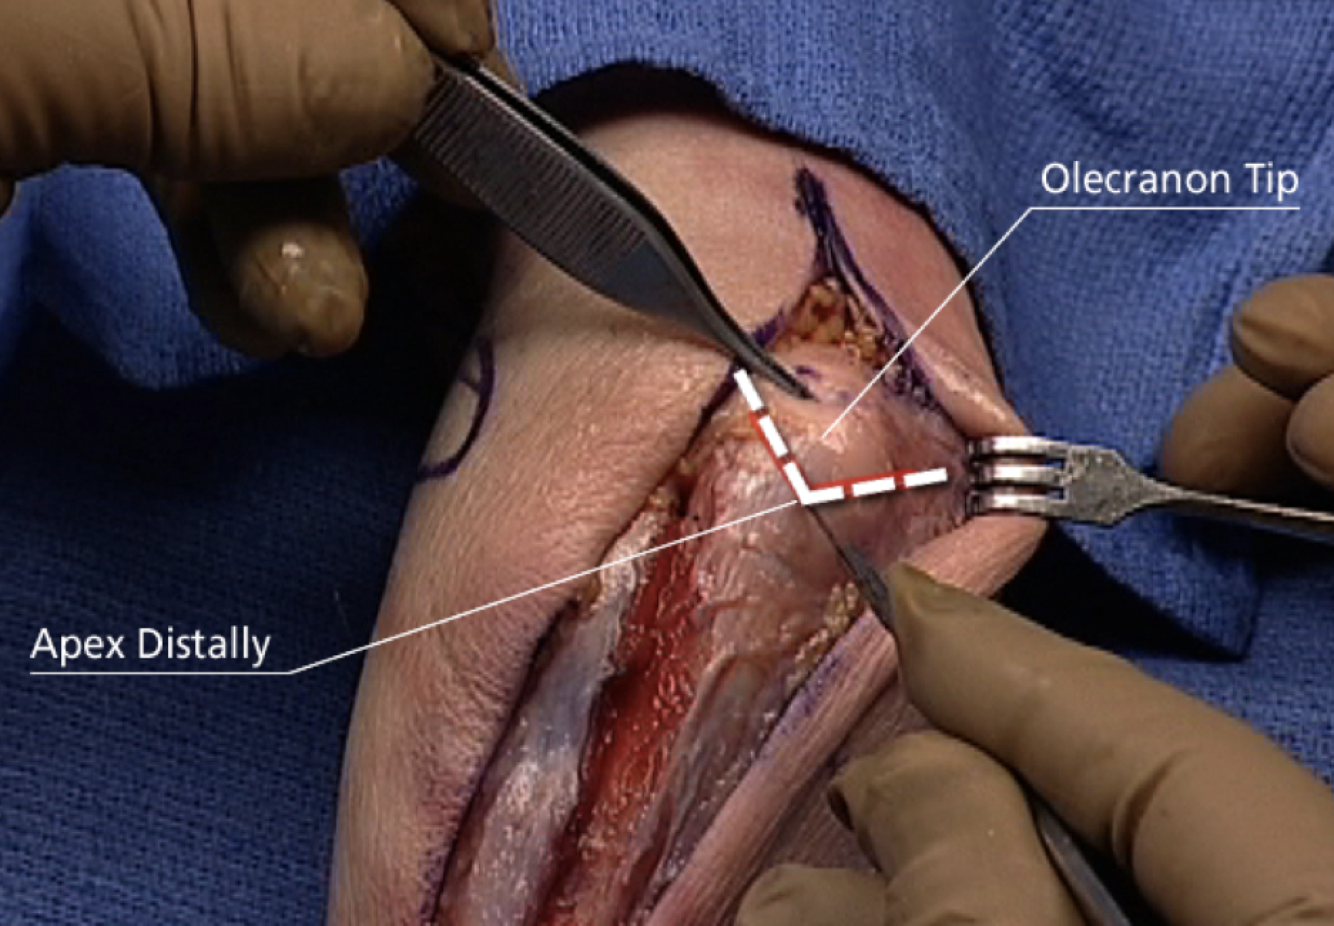

Olecranon Osteotomy

Interval: n/a

Approach: Apex distal osteotomy ~2cm distal to olecranon tip. Into “bare area” of sigmoid notch. Saw 1/2- 2/3 of the way in, then finish with osteotome to get interdigitation. Can predrill olecranon to give good reduction after. Can extend from a paratriciptal/triceps split.

Dangers: Articular surface distal humerus/ulna.